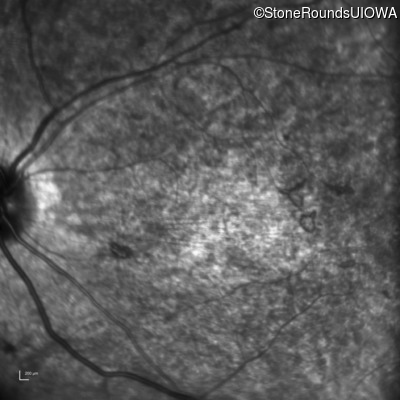

Infrared Fundus Photograph - Right - 20/400 sc

Exemplar